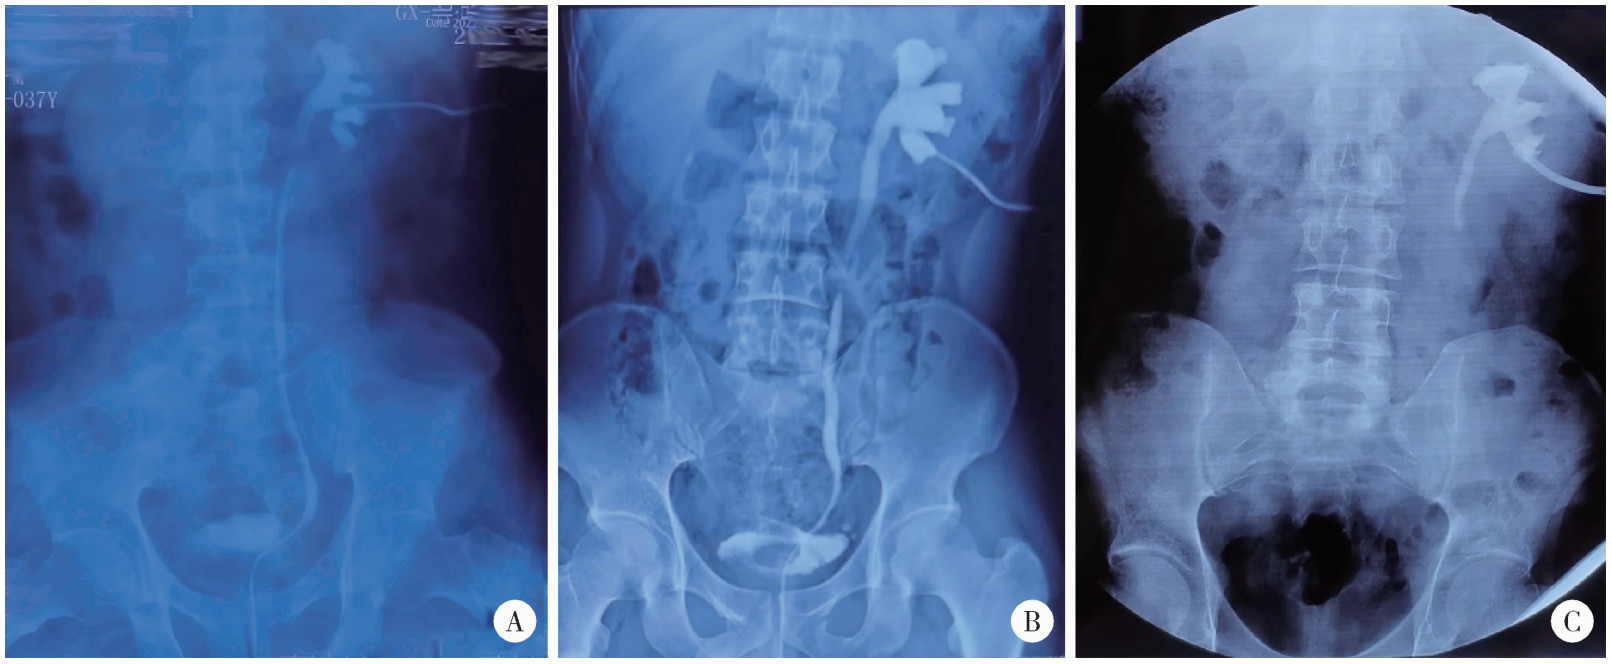

Figure 2

Different surgical strategies for stone related ureteral stricture A, ureteroureterostomy; B, ureteral reimplantation (psoas hitch); C, autologous mucosal graft ureteroplasty; D, ileal ureter replacement."